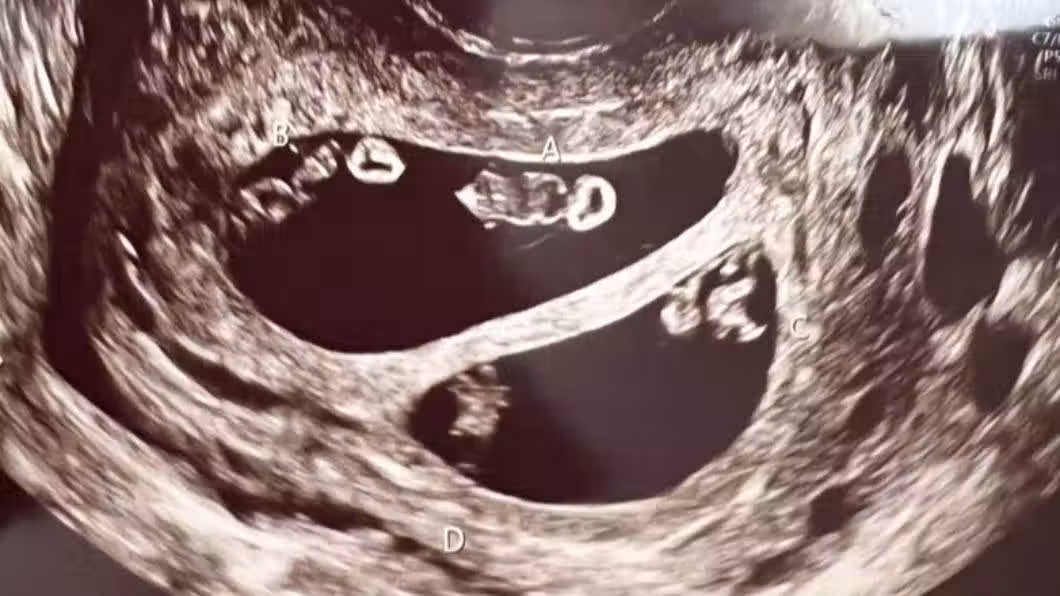

醫生在照超音波時發現驚人景象,艾希莉本來以為自己是懷著一對雙胞胎寶寶,沒想到醫生疑惑的看著螢幕好久,又走出房間請同事一起來觀察,最後才確定她竟然懷上了2對同卵雙胞胎,分別為2男2女,而醫師也解釋這狀況在醫學上發生機率僅7千萬分之一,根本就像是中了一張大樂透般不可思議!